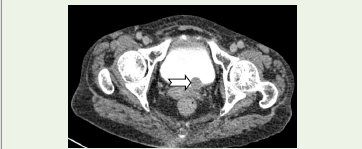

The mass showed extension into the proximal and mid left ureter with resultant dilatation, while the distal ureter appeared normal. An additional lesion was noted at the left vesicoureteric junction, producing a filling defect within the urinary bladder [Figure 2]. Enlarged left renal hilar lymph nodes were identified. Associated findings included mild hepatomegaly with multiple hypodense lesions suggestive of metastases [Figure 3] and splenomegaly.

Figure 2:CT Axial delayed phase: Left vesicouretric junction shows a similar

attenuation mass (white arrow) causing a filling defect in the urinary bladder.